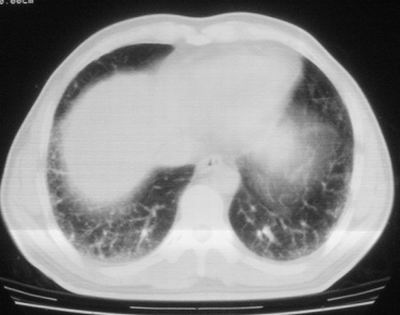

患者,男,44岁,糖尿病4年余,近期消瘦、乏力。化验检查:总胆红素26.33(参考值:5.1-17.2u mol/l),直接胆红素:6.4(参考值:0-4.3u mol/l),谷-丙转氨酶(alt):843(参考值:<40u/l),hbsag(+),抗hbs(-),hbeag(-),抗-hbe(+),抗-hbc(+)。

1\\粟粒性肺结核可能性大,支气管肺泡癌不排除

2\\少量腹水

双肺散在小结节影,考虑粟粒性肺结核.肺窗薄扫会更好看些.

双肺外侧带胸膜下可见网状阴影,考虑轻度肺间质纤维化。

双肺纹理增强并可见网格状影达外带,考虑双肺感染并轻度间质纤维化

1.双肺急性粟粒型肺结核;2.少量腹水.

肺间质纤维化并肺部感染,结合不能排出,毕竟糖尿病人易合并之,建议结合ppd检查或hrct进一步扫描。